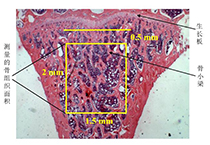

• 骨形態(tài)學(xué)測(cè)量分析案例